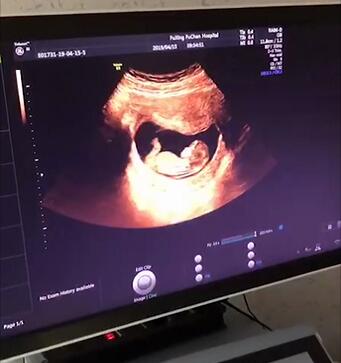

1、超声波检查

孕5~6周,通过超声波检查,大致能看到胚囊在子宫内的位置,筛查是否有宫外孕的可能。另外,在孕期5~8周间,还可以看到胚胎数目,以检查是否孕育了多胞胎!

4、超声影像(四维彩超)

孕22—26周,对胎儿进行超声影像(四维彩超)检查,不仅可以看到宝贝的体态、神情,探秘宝贝宫内生活,而且能及时筛查胎儿是否存在先天性结构异常,并为筛查先天性心脏疾病提供科学依据。